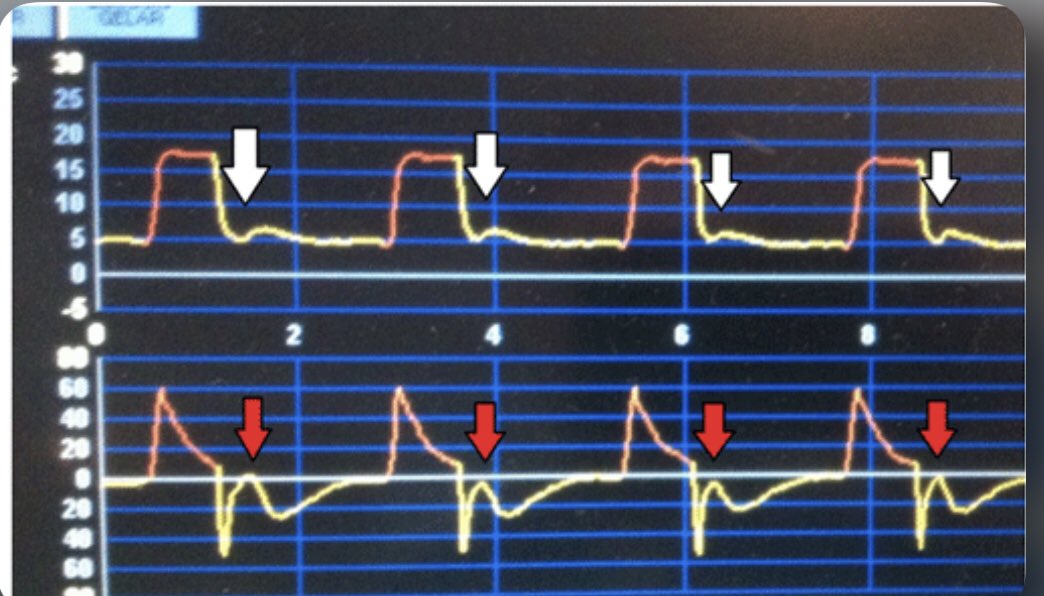

1- ineffective efforts

1- ineffective effort أو المحاولة الغير كافية.

- يقوم المريض بمحاولة سحب هواء " غير كافية" بأن يقوم الجهاز بالإحساس فيها.

- قد يحدث خلال الشهيق او الزفير.

أسبابها:

• وضع وقت شهيق اطول من اللازم.

• وضع وقت زفير أقل من اللازم.

- تستطيع الكشف عنه من خلال رؤية flow waveform

2- double triggering

- تحدث عندما يقوم الجهاز بإيصال نفسيين متتاليين بدون وجود وقت زفير كافي بينهم

-الأسباب:

•وقت الشهيق الموضوع من قبل المختص أقصر من الوقت الذي يقوم المريض بطلبه، فيستمر المريض بطلب شهيق.

• (Vt) الموضوع من قبل المختص أقل من الذي يطلبه المريض.

4- late cycling to exhalation.

تحدث عندما يقوم الجهاز بتأخير حدوث الزفير. حيث يقوم الجهاز بتخطي طلب المريض للزفير.

الأسباب:

• طول وقت الشهيق الموضوع من المختص.

•التسريب ( leak)

•E sens موضوعه أقل من اللازم.

تستطيع رؤية هذا الخلل في Flow waveform أو pressure waveform.

5- Flow asynchrony

- يحدث عندما يكون مستوى التدفق الموضوع من المختص أقل من اللازم.

- خطأ وارد بكثرة عند استخدام volume control breath type.

- dip and spike ظاهرة التي تظهر في pressure waveform